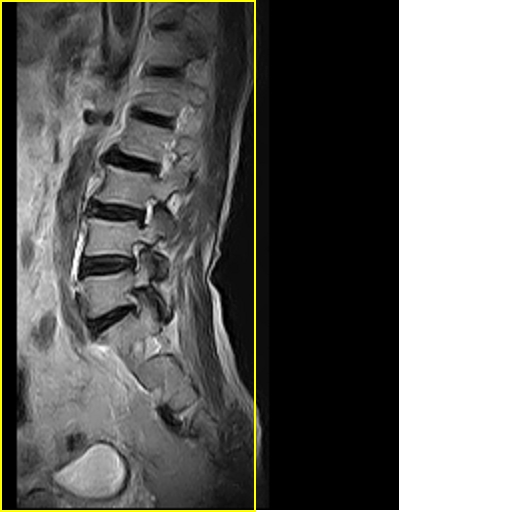

男,78岁,右下肢跛行两月.

腰间盘膨出、黄韧带肥厚、可疑先天性腰椎管狭窄。

退行性骨关节病:增生、椎间盘变性、膨出...

退行性病变:增生、椎间盘变性、膨出[l4-5、l5-s1 椎间盘膨出]

退行性骨关节病:增生、椎间盘变性、膨出..黄韧带肥厚.